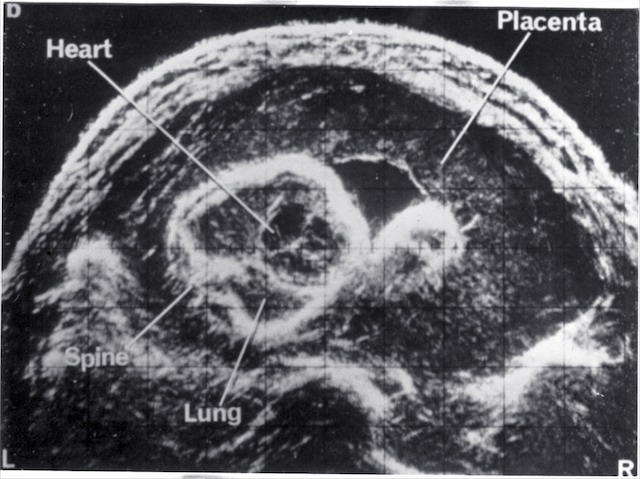

- Fetal anatomy

| 1968 | Demonstration of fetal orbits, heart, bladder, kidneys and scrotum |

| 1970 | Introduction of grey scale ultrasound, improving dramatically the demonstration of normal and abnormal structures in the fetus, placenta and mother |